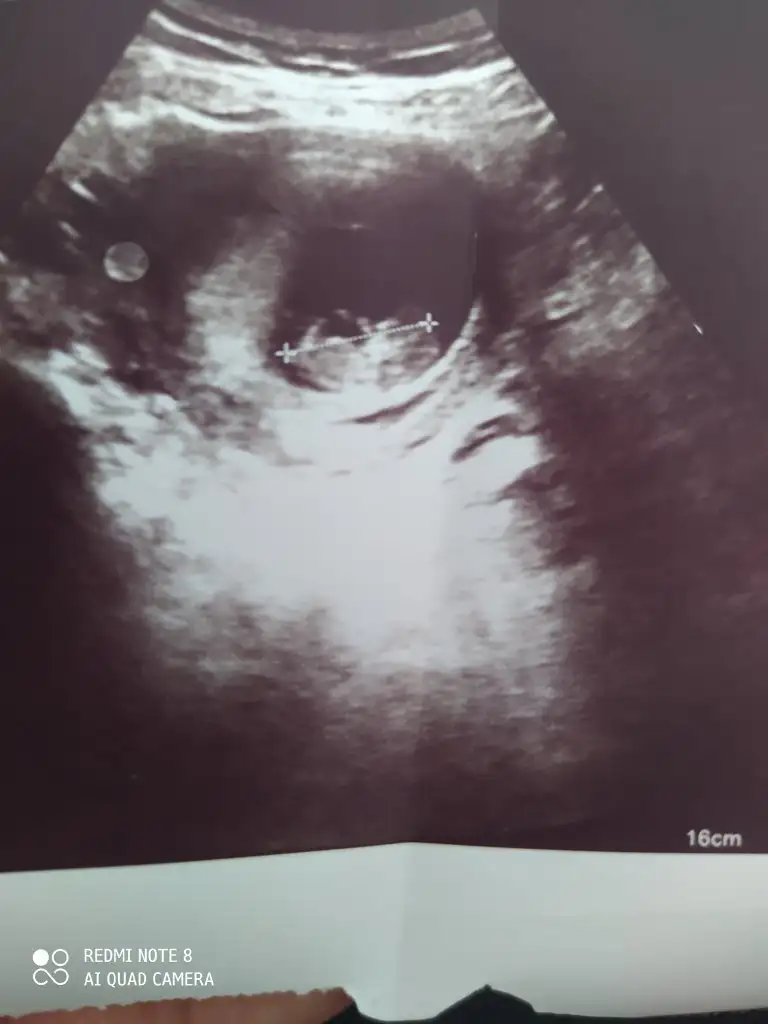

12+3 bankada tahmin de bulunurmusunuz